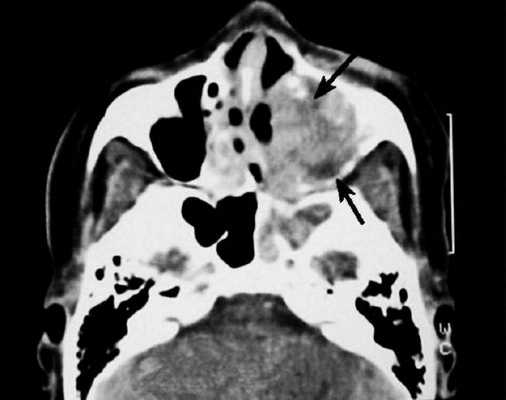

Плоскоклеточный рак на КТ носовых пазух с контрастом. Ткань опухоли отмечена длинной стрелкой, деструктивные изменения кости левого верхнечелюстного синуса - короткой.